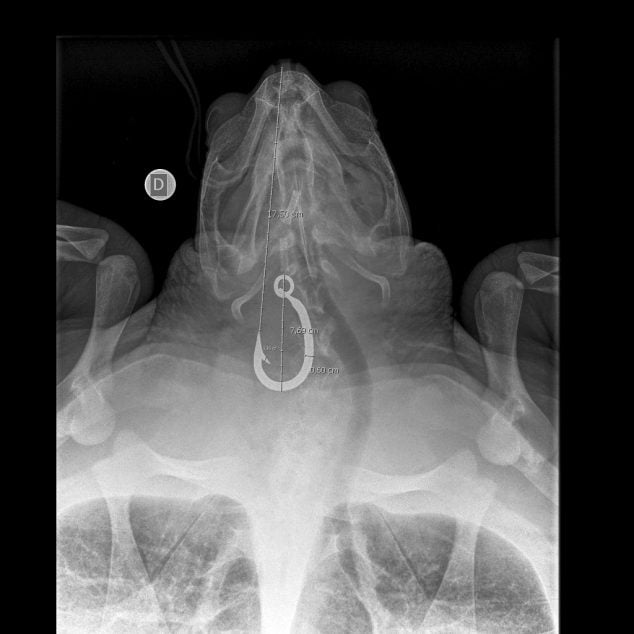

Carmencita, invece, è stata rinvenuta alla deriva da diportisti a circa 15 miglia dalla costa, fra Ponza ed Anzio. Nonostante il suo peso fosse di 31 Kg, compatibile con quello di un esemplare di circa 15 anni di età, seppure non ancora adulto, è stata issata a bordo ed immediatamente trasportata presso il centro di primo soccorso di Zoomarine. Carmencita aveva un grosso amo infisso in esofago e la lenza che le fuoriusciva dalla ranfoteca ed era imbrigliata a tubi di plastica pesanti al punto da averle procurato lesioni serie, con frattura dell’osso della mascella. Una volta trasferita presso il CRTM della Stazione Zoologica A. Dohrn di Napoli, la tartaruga è stata sottoposta ad un intervento chirurgico per la rimozione dell’amo che, fortunatamente, si è riuscito ad estrarre attraverso la bocca. Liberata ha potuto riprendersi ed è guarita perfettamente. Ormai anche Carmencita è pronta per tornare nel suo ambiente naturale.